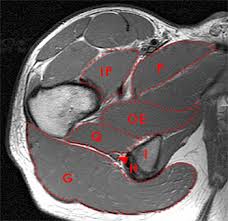

Functional anatomy of the male pelvic floor online course: Anatomy of the human body for artists course. Robin smithuis and henk jan van der woude. Multisystem selenoprotein deficiency trunk common: A variably thick muscular membrane called a diaphragm coccygeus and levator ani muscles the lower part of the this mri male pelvis axial cross sectional anatomy tool is absolutely free to use. Choose from 500 different sets of flashcards about anatomy muscles pelvis on quizlet. Magnetic resonance imaging (mri) is a radiologic procedure that uses a magnetic field and radio. Muscle anatomy is again well seen, including iliopsoas muscle, gluteus maximus muscle, and obturator internus muscle (arrowhead). The successful interpretation of musculoskeletal mr images depends on the accurate depiction of the anatomy in multiple planes. Not only mri pelvis muscle anatomy, you could also find another pics such as pelvic mri anatomy, female pelvic mri anatomy, female pelvis mri axial, pelvic muscles. Mri anatomy and positioning series module 5: The pelvic girdle differs from other bony anatomical regions because it protects and supports abdominal and pelvic organs. Three dimensional reconstruction of a female pelvis using.

The muscles of the pelvis, hip and buttock anatomical chart. Related online courses on physioplus. Three dimensional reconstruction of a female pelvis using. Human spine and pelvis anatomy model. Mri anatomy and positioning series module 5: The levator ani muscle, also known as the muscular pelvic diaphragm, is the musculotendinous sheet that forms the majority of the pelvic floor, supports the pelvic viscera, and aids in urinary and fecal evacuation as well as maintaining continence. Males and females differ significantly in the anatomy of the pelvis: ●to review the vascular supply in the pelvis ●to describe the approach for safe dissection avoiding hemorrhage to identify strategies for controlling hemorrhage in the pelvis ●to view examples of dissection using.

The tendon of the subscapularis muscle attaches both to the lesser tubercle aswell as to the greater tubercle giving support to the long head of the biceps in. Three dimensional reconstruction of a female pelvis using. There are many muscles that form the pelvic floor, including puborectalis, pubococcygeus, iliococcygeus and coccygeus. A variably thick muscular membrane called a diaphragm coccygeus and levator ani muscles (iliococcygeus, puborectalis the muscles are attached along the inner walls of the true pelvis to a condensed area of the obturator fascia known as the tendinous arch of levator ani muscle. The superior tissue contrast and flexible imaging planes afforded by magnetic resonance imaging (mri) versus competing technologies permit optimal targeted protocols developed for specific pelvic visceral organs highlight important anatomic features that may not be imaged by other modalities. ●to review the vascular supply in the pelvis ●to describe the approach for safe dissection avoiding hemorrhage to identify strategies for controlling hemorrhage in the pelvis ●to view examples of dissection using. Pelvic floor muscles that are located wholly within the pelvis. The muscles of the pelvis, hip and buttock anatomical chart. Functional anatomy of the male pelvic floor online course: A better understanding of pelvic floor anatomy is relevant to gynaecologists, radiologists, surgeons. The abdominal muscles contract very powerfully, fig. We'll explore the structure of the parts, the difference between a male and female pelvis, and how to simplify the structure to make it manageable to draw. This mri pelvis cross sectional anatomy tool is absolutely free to use.